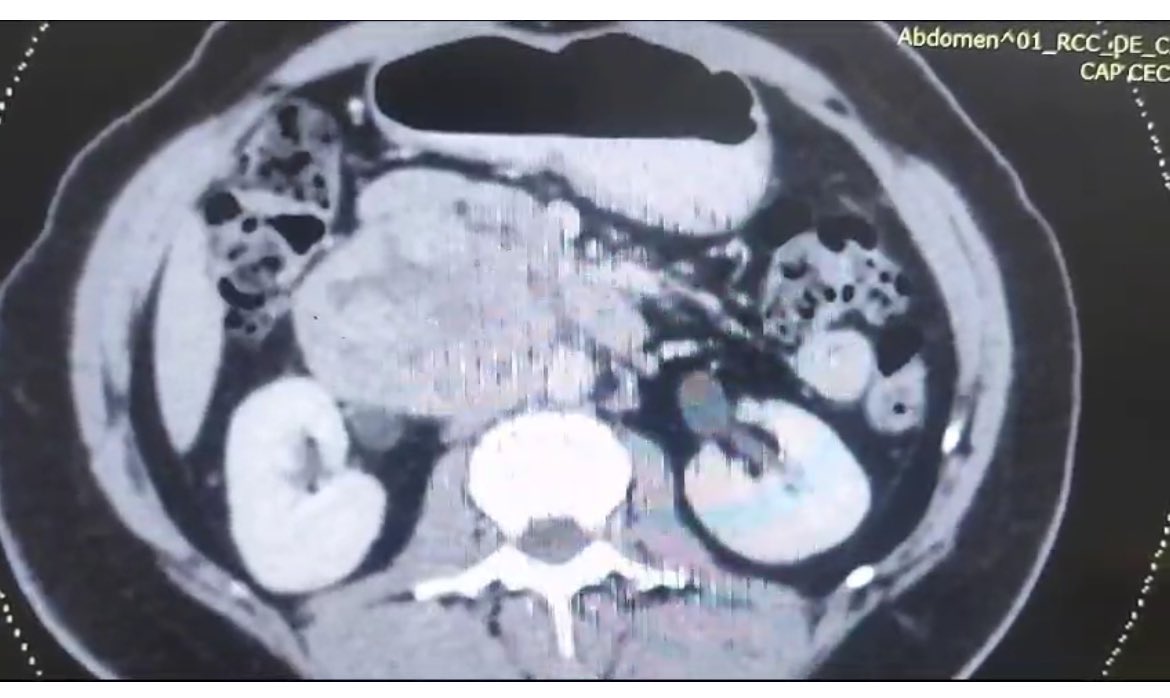

A 62/M COPD pt with Type 5 TAAA under went Hybrid TEVAR. Link for surgery in this link -youtu.be/cVKjV5J8YFk